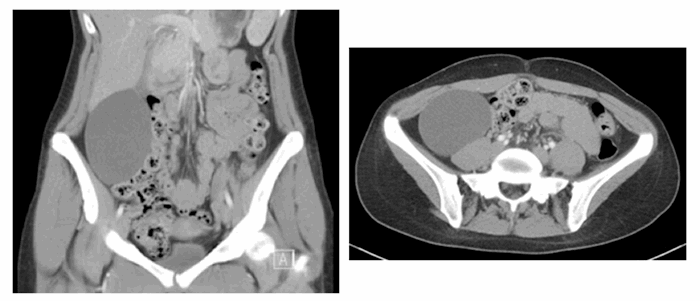

A 24-year-old woman with an uncomplicated medical history presented complaining of right upper quadrant fullness and discomfort. After delivery of her second child in 2017, the patient noticed a palpable mass in the right abdomen, which became progressively more bothersome. Abdominal and pelvic CT scan obtained in early 2018 showed an 11 cm x 7 cm x 6 cm cystic mass in the right colic gutter concerning for enteric duplication cyst. The mass appeared thin-walled, smooth and contained few septations (Figure 1).

Figure 1. Large, right-sided, cystic mass in axial and coronal views